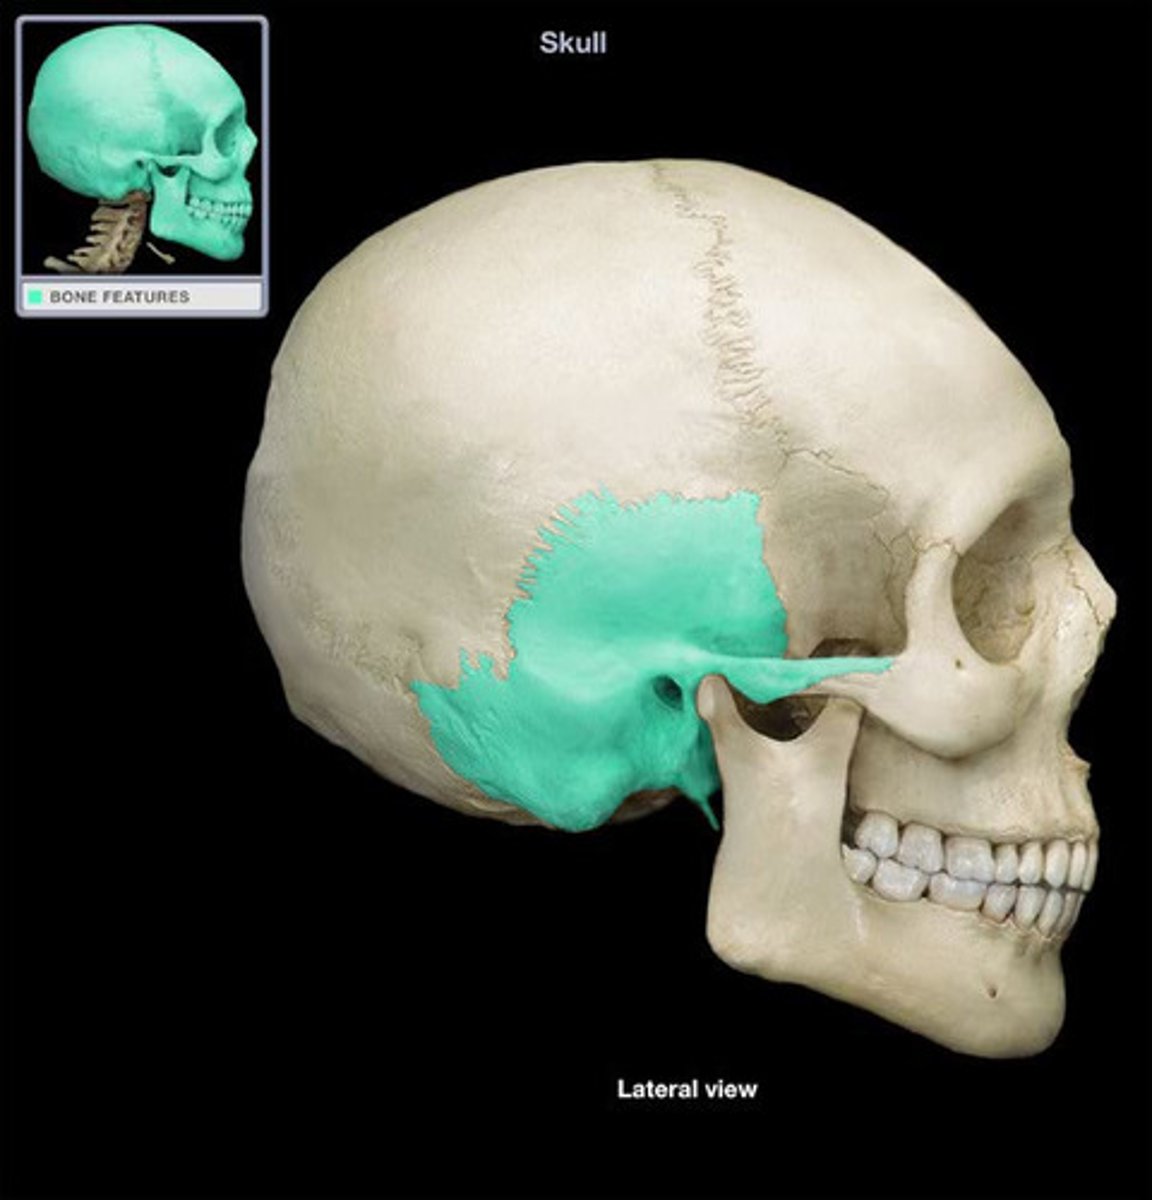

Temporal Bone

Temporal Bone

Zygomatic arch

Mastoid Process

Mastoid Process

External Auditory Meatus

External Auditory Meatus

Mandibular Fossa

Styloid Process

Stylomastoid Foramen